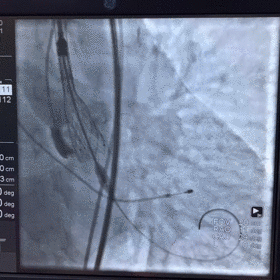

术中影像

图片

根部造影

球囊预扩

瓣膜释放至2/3造影观察

瓣膜释放后形态欠佳

经球囊后扩后瓣膜形态良好

手术结果

术后造影及超声探查未见瓣周漏,跨瓣压差术前183mmHg,术后几乎无压差,术中及术后未出现相关并发症,手术圆满完成。